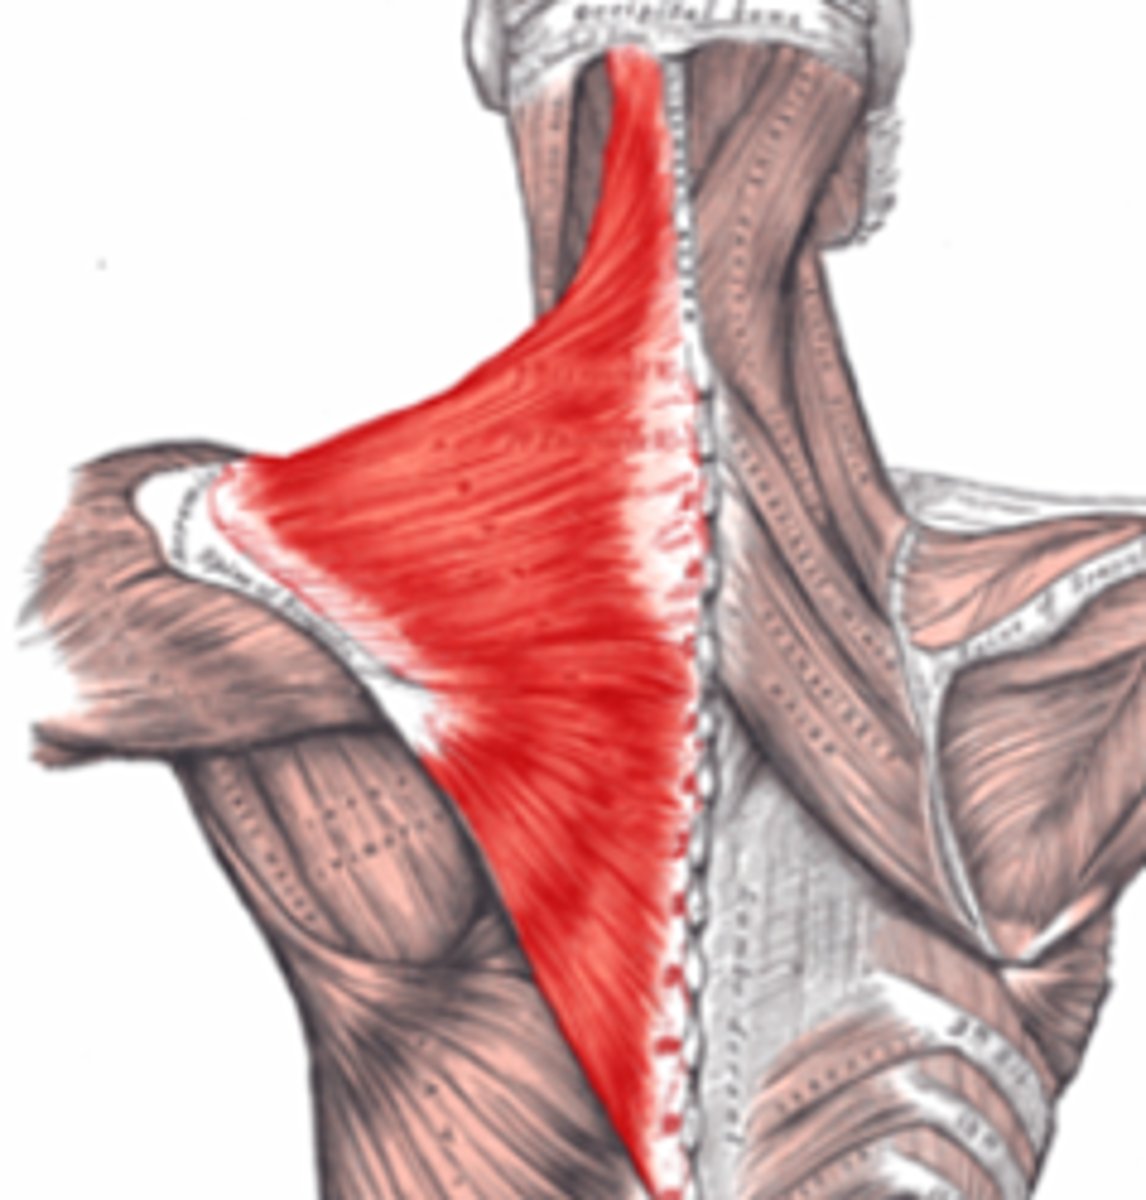

trapezius

draw head back